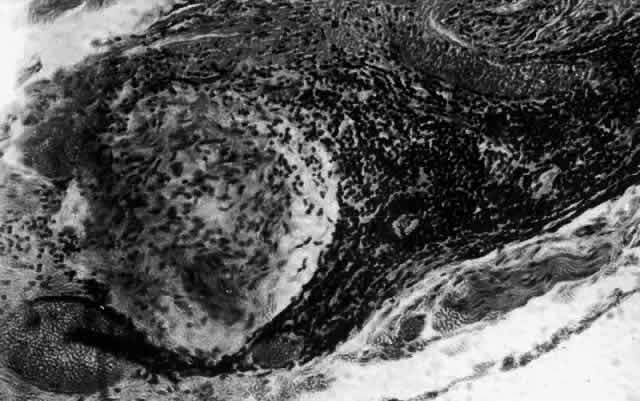

What is clinically represented solely by inflammation and edema is histopathologically a granulomatous lesion of the sclera, the center of which consists largely of plasma cells, lymphocytes, and mast cells (Figs. 21 through 23). Foster and colleagues have identified the cellular subsets and glycoproteins in both necrotizing and non-necrotizing scleritis.22 This shows an active T-cell inflammatory response with a high CD4/CD8 ratio and increased HLA/DR and CD14, indicating a macrophage-induced response that would lead to granuloma formation. Remote from the granuloma, the fibrocytes of the sclera become activated, the proteoglycan adjacent to them becomes altered, and the collagen fibrils of the sclera become unraveled (Figs. 23 and 24). These changes appear to take place prior to the invasion of the stroma by cells of the granuloma.20 The vessels in and around the necrotic area show medial necrosis and perivascular cuffing with lymphocytes, and endothelial swelling with microvascular occlusion. Ninety-six percent of the specimens examined by Foster and associates show a microangiopathy characterized by a neutrophil infiltrate in and around the vessel wall.22–23 This is most obvious at the center of the lesion where there may be occlusion of the vessel, thrombosis, or even aneurysm formation (Fig. 25). From these pathologic investigations, clinical observations, animal experiments, and the results of fluorescein angiography, it would appear that the scleral inflammation is initiated either by trauma (be it accidental or surgical)23–25 or by bacterial or viral infection. If circulating immune complexes are present because of the poor blood flow, they become precipitated in and around the vessel walls in the area of inflammation. In other patients, a persistence of tissue damage will lead to autoimmunization. Damage to the endothelial cells of the microvasculature leads to changes within the vessels detectable on angiography and to catabolic changes in the surrounding tissues. These changes, in turn, allow the granulomatous response that is seen in histopathologic sections, the first detectable change being in the scleral fibrocytes and the proteoglycan and collagen remote from the site of cellular infiltration.

Fig. 21. Advancing edge of a granulomatous reaction. Scleral fibers are split and separated by edema and then disrupted when invaded by the granuloma

Fig. 22. Electron micrograph of an area of active scleritis showing the plasma cell infiltrate suggestive of an immune response. Note aggregated plasma cells, with the characteristic whorled rough endoplasmic reticulum, in the process of degeneration, releasing organelles and nuclear debris into the extracellular matrix. (Uranyl acetate and lead citrate. X3000) (Courtesy of Dr. R. Tripathi)